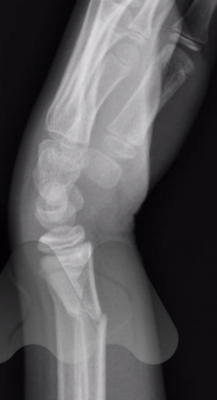

Wrist fractures can develop bruising and swelling in the wrist and fingers and sometimes there is an obvious deformity in the wrist (dinner-fork deformity). An x-ray can often confirm the diagnosis. IN subtle or complete fractures, a CT scan may be required to confirm the diagnosis or help plan the treatment.

Fractures sometimes involve the joint surface (intra-articular) or break the bone outside the joint (extra-articular).